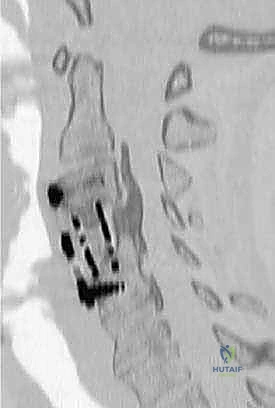

* Computed Tomography (CT): Superior for bony anatomy, especially for evaluating ossification of the posterior longitudinal ligament (OPLL).

FIG 2 • C. Sagittal CT reconstruction showing large ossified posterior longitudinal ligament extending from C2 to C6. There is evidence of failed anterior decompression by an outside facility.

FIG 2 • D. Axial CT image demonstrating vertebral canal compression from large ossified posterior longitudinal ligament.